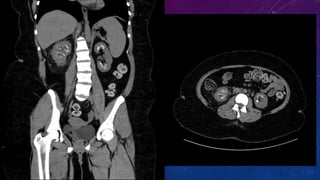

CYSTIC RENAL DISEASE